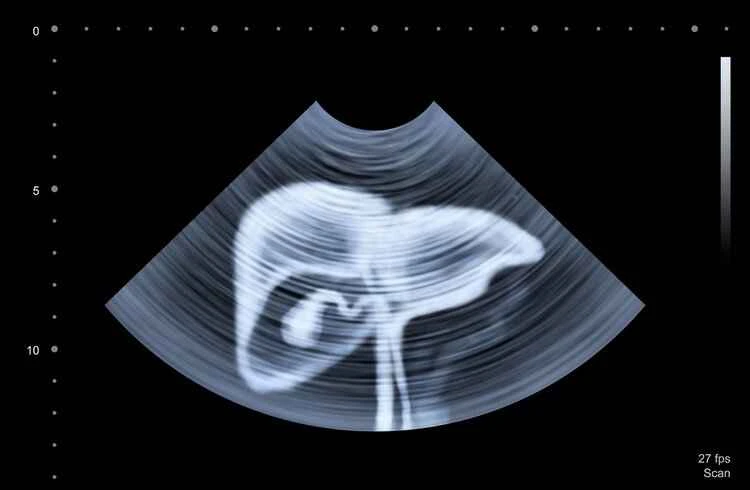

One method is to check for the tumor marker AFP (alpha-fetoprotein), and the other is to have an ultrasound .

It should be noted that relying solely on AFP (alpha-fetoprotein) levels cannot definitively diagnose early-stage liver cancer, nor can an ultrasound alone provide a highly accurate diagnosis. This is because ultrasound has limited penetration and low resolution, making some liver cancers difficult to detect. Furthermore, interpreting ultrasound images heavily relies on the doctor's experience. Therefore, combining both methods will result in a higher accuracy rate in diagnosing liver cancer. In necessary cases, additional examinations may be required for definitive diagnosis.